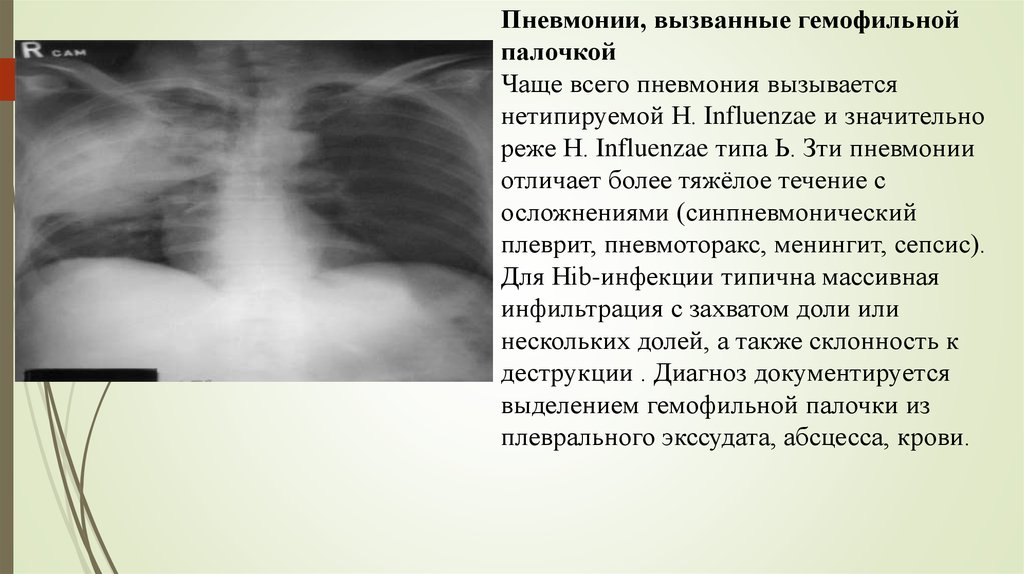

Фотографии бактерий, вызывающих бактериальные пневмонии у животных

Раздел: Другие животные